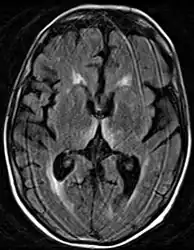

Brain atrophy associated with WKS occurs in the following regions of the brain: the mammillary bodies, the thalamus, the periaqueductal grey, the walls of the 3rd ventricle, the floor of the 4th ventricle, the cerebellum, and the frontal lobe. In addition to the damage seen in these areas there have been reports of damage to cortex, although it was noted that this may be due to the direct toxic effects of alcohol as opposed to thiamine deficiency that has been attributed as the underlying cause of Wernicke-Korsakoff Syndrome.[28]

Frequently, secondary to thiamine deficiency and subsequent cytotoxic edema in Wernicke encephalopathy, patients will have marked degeneration of the mammillary bodies. Thiamine (vitamin B1) is an essential coenzyme in carbohydrate metabolism and is also a regulator of osmotic gradient. Its deficiency may cause swelling of the intracellular space and local disruption of the blood-brain barrier. Brain tissue is very sensitive to changes in electrolytes and pressure and edema can be cytotoxic. In Wernicke this occurs specifically in the mammillary bodies, medial thalami, tectal plate, and periaqueductal areas. Sufferers may also exhibit a dislike for sunlight and so may wish to stay indoors with the lights off. The mechanism of this degeneration is unknown, but it supports the current neurological theory that the mammillary bodies play a role in various "memory circuits" within the brain. An example of a memory circuit is the Papez circuit.